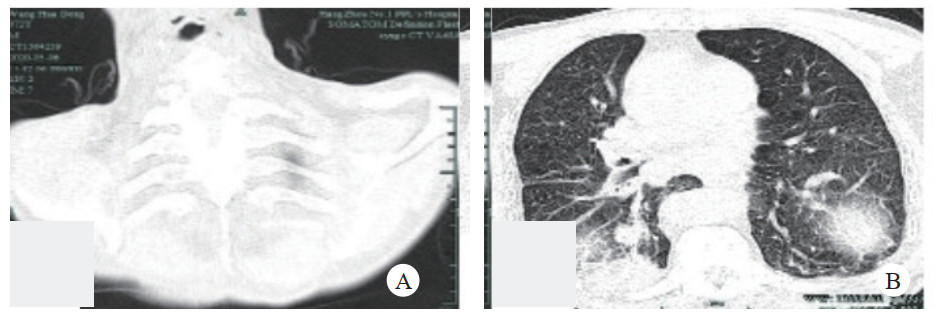

病例2:患者,男性,72岁,退休人员。因“反复咳嗽胸闷20余年,再发半月。”于2020年5月4日入院。既往有强直性脊柱炎50年,未予治疗;曾在外院诊断慢性阻塞性肺病,间断使用吸入性糖皮质激素(ICS)联合长效肾上腺能激动剂(LABA)治疗。吸烟史50年,1包/d,戒烟1年。查体:体温: 36.5℃,脉搏: 72次/min,呼吸21次/min,血压131/75 mmHg。神清,口唇无发绀,浅表淋巴结未及肿大,气管居中,桶状胸,肋间隙增宽,双肺呼吸活动度明显减低,双肺叩诊呈过清音,双肺呼吸音低,未闻及干湿性啰音。心律齐,心率72次/min,未闻及杂音。双下肢无浮肿,可见杵状指,脊柱侧弯和后凸畸形。

辅助检查:血白细胞5×109/L,中性粒细胞73.2%,淋巴细胞14.2%,血红蛋白125 g/L,血小板172×109/L;生化示白蛋白37.8 g/L,球蛋白26.2 g/L,肌酐122 μmol/L,其余正常。血肿瘤指标神经烯醇化酶29.3 μg/L(参考值0~16.6 μg/L),细胞角蛋白19片段4.9 μg/L(参考值0~3.5 μg/L),癌胚抗原61.26 μg/L(参考值0~5 μg/L),胃泌素释放肽前体4 145.93 ng/L(参考值0~65 ng/L)。血气分析: 酸碱度7.373,二氧化碳分压50.9 mmHg,氧分压60.2 mmHg,实际碳酸氢根28.9 mmol/L,全血剩余碱3.3 mmol/L。心脏超声检查结果: 左房增大,主动脉瓣少量反流反流反流反流反流,主动脉管壁上多发硬化斑,二、三尖瓣少量反流反流反流反流反流,左室舒张功能减退。肺功能示极重度阻塞性通气功能障碍。胸部CT示“右肺下叶结节影,直径2 cm,纵隔、右肺门多发肿大淋巴结;右侧少量胸腔积液伴右肺下叶肺不张。(见图 3)”入院诊断“①肺占位性病变; ②慢性阻塞性肺病; ③动脉粥样硬化; ④强直性脊柱炎。”

| 见颈椎及上段胸椎明显前屈,右下叶结节,两侧膈肌抬高 图 3 病例2 2020年5月6日胸部CT可 |